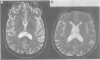

OBJECTIVES: To compare the results of clinical assessment and MRI with neuropathological findings in the diagnosis of HIV and cytomegalovirus (CMV) associated CNS disease. METHODS: A retrospective study of 35 patients infected with HIV who were examined at necropsy between four and 70 (median 20) days after neurological assessment and MRI. RESULTS: Of the 35 patients, 19 had diffuse white matter hyperintensity on T2 weighted MRI, six of whom also had focal lesions. Nine other patients had focal white matter lesions and seven had changes in cortical atrophy only. Necropsy in the 19 with diffuse white matter hyperintensity showed HIV leukoencephalopathy (HIVLEP) with encephalitis in 10, CMV encephalitis in three, both HIVLEP/HIV encephalitis and CMV encephalitis in one, lymphoma in three, and non-specific inflammation in two. Necropsy in the 16 other patients without diffuse white matter hyperintensity showed CMV encephalitis in six, HIV encephalitis (without HIVLEP) in two, CMV encephalitis and HIVLEP/HIV encephalitis in one, non-HIV associated abnormalities in five, herpes simplex encephalitis in one, and lymphoma in one. CMV DNA was detected in CSF of five of seven patients with CMV encephalitis and in two of two with CMV associated polyradiculopathy but without CMV encephalitis. Diffuse white matter hyperintensity on MRI had a sensitivity of 100%, a specificity of 66.6%, and a positive predictive value of 58% for diagnosis of HIVLEP. CONCLUSION: Diffuse white matter hyperintensity on MRI can be due to either HIV or CMV associated pathology or non-specific abnormalities.